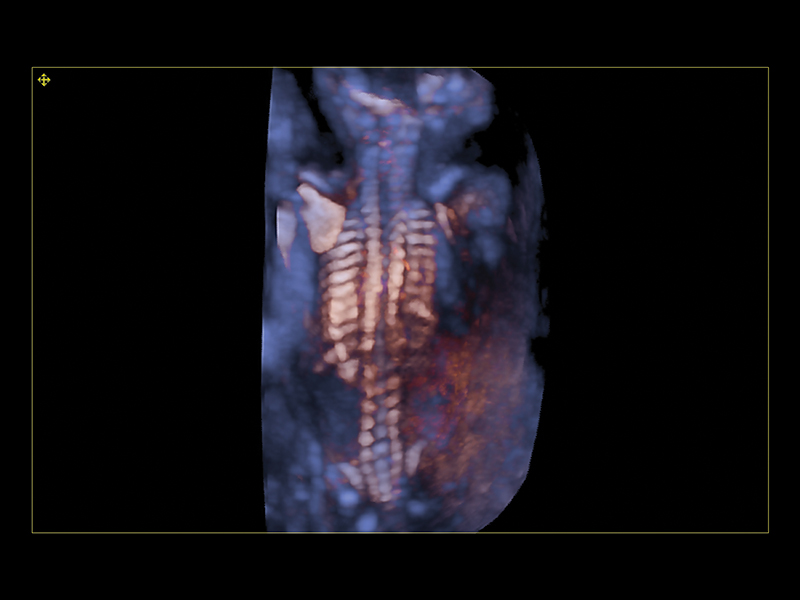

Realistic 3D/4D Depiction of the Fetus

Esaote attaches great value to the quality of its 3D/4D imaging in order to provide very detailed picture of the baby’s features, depending on the stage of fetal development. Its environment is provided by different modalities, based on how the volume can be processed and rendered.

Esaote XLight technology, with its realistic diffusion effects and shadows, emphasizes the anatomical details of the fetus in baby face scanning; XGlass creates a transparency effect; bone rendering is ideal to study the baby’s spine; TSI (Thick Slice Imaging) is suitable for well-defined and confined structures, such as the corpus callosum; finally, XSTIC accurately evaluates the fetal heart.

Clinical Images